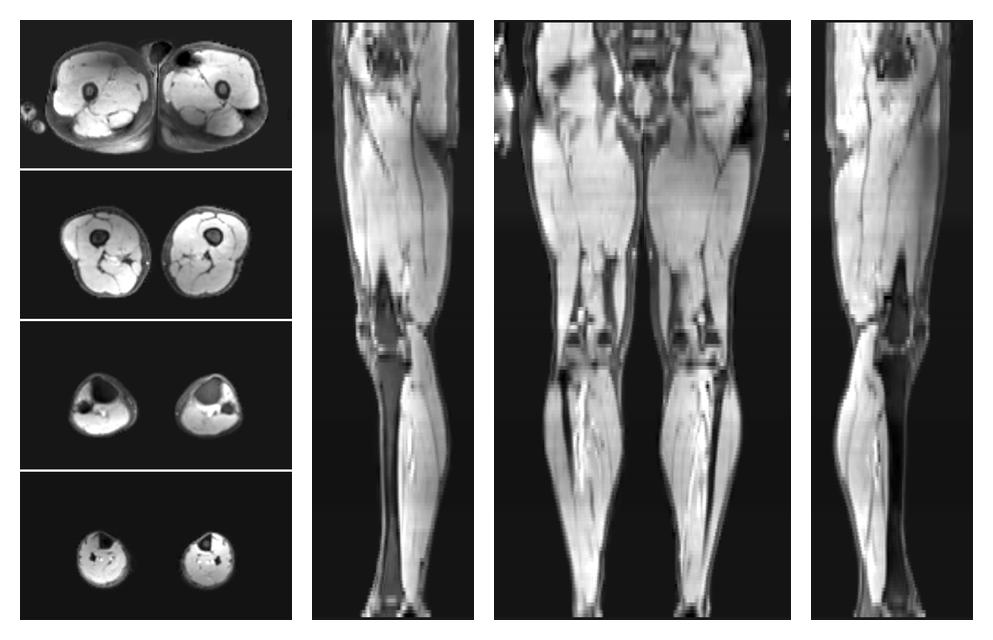

• Water only signal

The water part of the acquired multi-echo spin echo data.

• Water only T2 relaxation time

The water only T2 relaxation time of the lower extremity obtained from multi echo spin echo t2 mapping with EPG based reconstruction.